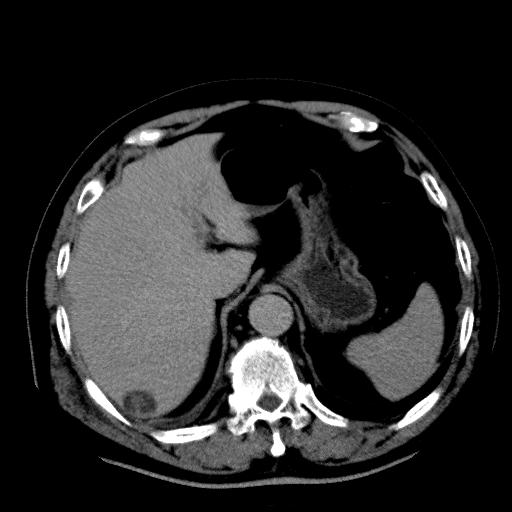

以下是引用zhctwbh在2008-8-23 14:20:00的发言:[br]囊肿合并出血

以下是引用zjb在2008-8-23 16:41:00的发言:[br]囊肿并出血可能性大。